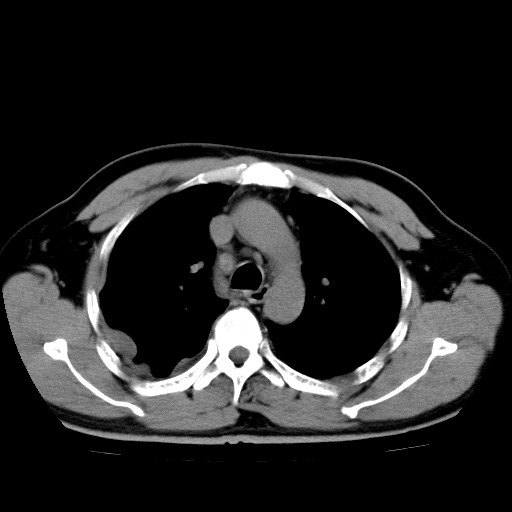

男,54岁,咳嗽,右侧胸痛10天。肺窗>150k,传不了

右肺中心型肺癌并右下肺不张,右侧胸膜纵隔转移。

右中央型肺癌并右肺下叶不张,纵隔内及右胸膜转移,右胸腔积液

右下叶大片实变,肺门未见明显肿块影。有胸腔积液和纵隔内肿大淋巴结影。没有增强和肺窗,不好定。

考虑:1、右下叶周围型肺癌伴胸膜、纵隔淋巴转移?

右下叶大片性阻塞性肺炎,肺门未见明显肿块影,纵隔内可见肿大淋巴结影,右见右侧胸腔积液及右侧胸膜增厚。

考虑:右侧中心性肺癌?伴纵隔淋巴结转移。建议上传肺窗。